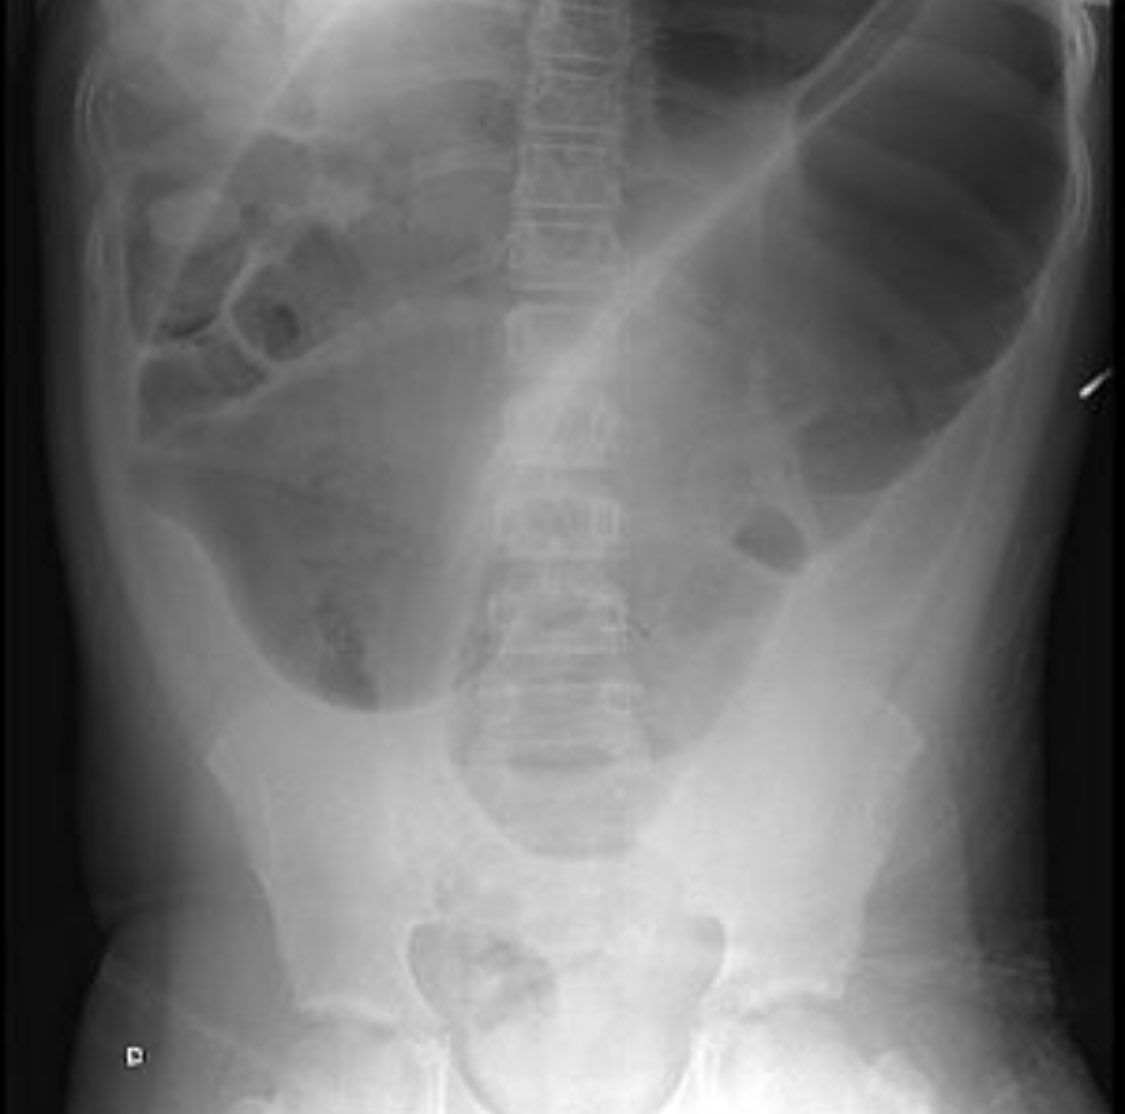

Coffee Bean Sign Volvulus . The proximal large bowel is also dilated (asterisks). The sigmoid colon is very dilated because it is twisted at the root of its mesentery in the left iliac fossa (lif). Specific signs, including a bent inner tube or a coffee bean sign, are characteristics of sigmoid. The coffee bean sign (also known as the kidney bean sign or bent inner tube sign) 4 is a radiological finding on an abdominal plain radiograph of a sigmoid volvulus although. Learn how to recognize sigmoid volvulus on abdominal imaging with the coffee bean sign and the whirl sign. [1] the coffee bean is: Abdominal radiography revealed a markedly distended loop of bowel measuring approximately 17 cm in diameter, consistent with what is known as the “coffee bean. Large bowel folded over itself and twisted in away that creates two. The twisted loop of sigmoid colon is said to resemble a coffee bean.

Coffee Bean Sign Volvulus Large bowel folded over itself and twisted in away that creates two. The proximal large bowel is also dilated (asterisks). Learn how to recognize sigmoid volvulus on abdominal imaging with the coffee bean sign and the whirl sign. Large bowel folded over itself and twisted in away that creates two. The coffee bean sign (also known as the kidney bean sign or bent inner tube sign) 4 is a radiological finding on an abdominal plain radiograph of a sigmoid volvulus although. Specific signs, including a bent inner tube or a coffee bean sign, are characteristics of sigmoid. The twisted loop of sigmoid colon is said to resemble a coffee bean. Abdominal radiography revealed a markedly distended loop of bowel measuring approximately 17 cm in diameter, consistent with what is known as the “coffee bean. [1] the coffee bean is: The sigmoid colon is very dilated because it is twisted at the root of its mesentery in the left iliac fossa (lif).

Coffee Bean Sign Volvulus The sigmoid colon is very dilated because it is twisted at the root of its mesentery in the left iliac fossa (lif). [1] the coffee bean is: The proximal large bowel is also dilated (asterisks). The twisted loop of sigmoid colon is said to resemble a coffee bean. Abdominal radiography revealed a markedly distended loop of bowel measuring approximately 17. Coffee Bean Sign Volvulus.